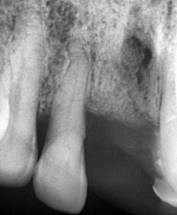

El paciente no refiere odontalgia, por lo que se presenta aparentemente asintomático al examen clínico. Dentro de las pruebas complementarias, se realizó la toma de una radiografía panorámica, donde se evidencio sobras radiolúcidas compatibles con reabsorción de la cresta ósea alveolar con patrón horizontal y vertical generalizado, también se visualizan sombras radiolúcidas alrededor de las raíces de las unidades dentales 1.2, 2.1 y 2.3, compatibles con procesos infecciosos y ensanchamiento del ligamento periodontal; además en la pieza 1.2 se complementó con una radiografía periapical en donde se observa una sombra radiopaca a nivel del tercio apical en el conducto radicular lo que podría indicar una posible calcificación y una sombra radiolúcida que rodea la raíz dental compatible con el posible ensanchamiento del ligamento periodontal; razón por la cual existe movilidad y menor soporte (Figura 2).

Figura 2. Radiografía panorámica y periapical de la pieza N.º 1.2

Elaboración: Los autores.